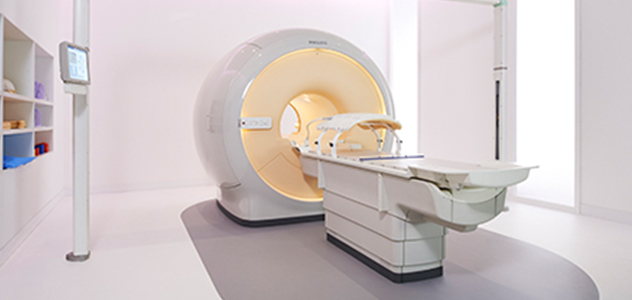

Beaumont Health System (Royal Oak, Michigan, USA) is one of the largest health systems in the USA, with eight hospitals and 153 outpatient sites, a medical school and a research institute. The Radiation Oncology (RO) department houses a dedicated Ingenia MR-RT solution that is routinely used for clinical and research MR-RT activities. “The main reason to integrate MR imaging in RT planning is the superb soft tissue contrast that allows detailed delineation of tumors and healthy organs, which is crucial for RT planning,” says Craig W. Stevens MD, PhD. “MR also provides information on functional and biological activities in tumors, background tissue and normal organs, which may also be used in RT planning,” says physicist Di Yan, DSc, FAAPM.” “We currently use MR-RT mainly in the abdomen and pelvis region: prostate, colorectal, pancreatic, cervical, and liver. Also in the brain, we are starting to use it,” says Dr. Yan.

“There are some general challenges in RT imaging – even with CT – such as imaging geometry and positioning accuracy. Positioning is extremely important in RT, because we need reproducibility between imaging and treatment position. We also need accurate geometry so we can be sure our treatment plan is properly delivered during the treatment,” says Dr Yan. “The Ingenia MR-RT configuration includes an external laser positioning system for patient alignment and a flat tabletop for imaging the patient in treatment position. Ingenia MR-RT also came with a special QA package for regular monitoring of precision. Our Ingenia 3.0T scanner achieves good geometric accuracy – within a millimeter for most patients – and the phantom measurement is even better,” he adds. “Ingenia’s wide 70 cm bore is valuable to easily accommodate immobilization devices needed in RT,” says Dr. Stevens. “With a small bore MR scanner you can’t get the RT immobilization devices into the scanner properly; the large bore makes it easy to image patients in their immobilization device.”